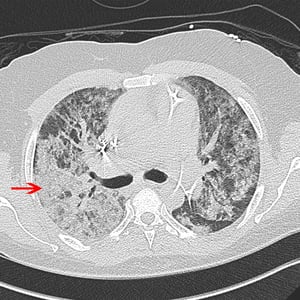

TC di un paziente con sindrome da distress respiratorio acuto

La freccia rossa indica le opacità alveolari diffuse in un paziente con sindrome da distress respiratorio acuto. Il paziente ha anche cardiomegalia, un defibrillatore automatico impiantabile a tre elettrocateteri con punte nel ventricolo destro, e un catetere di Swan Ganz con punta nell'arteria polmonare.

© 2017 Elliot K. Fishman, MD.